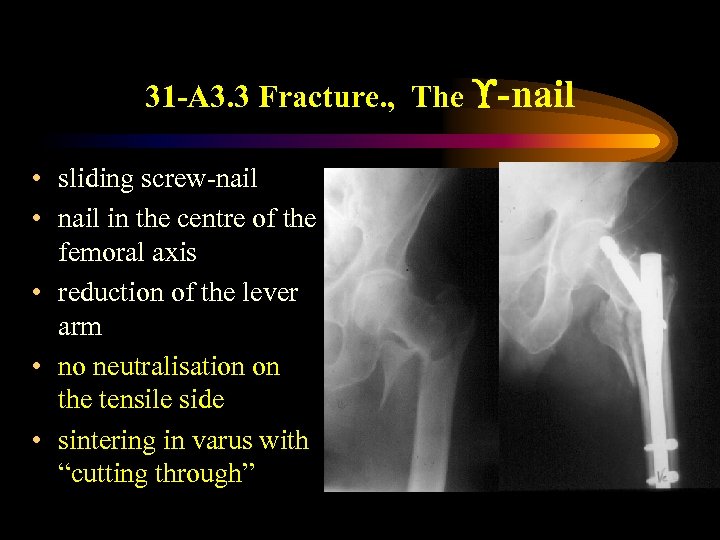

31 -A 3. 3 Fracture. , The -nail • sliding screw-nail • nail in the centre of the femoral axis • reduction of the lever arm • no neutralisation on the tensile side • sintering in varus with “cutting through”

31 -A 3. 3 Fracture. , The -nail • sliding screw-nail • nail in the centre of the femoral axis • reduction of the lever arm • no neutralisation on the tensile side • sintering in varus with “cutting through”